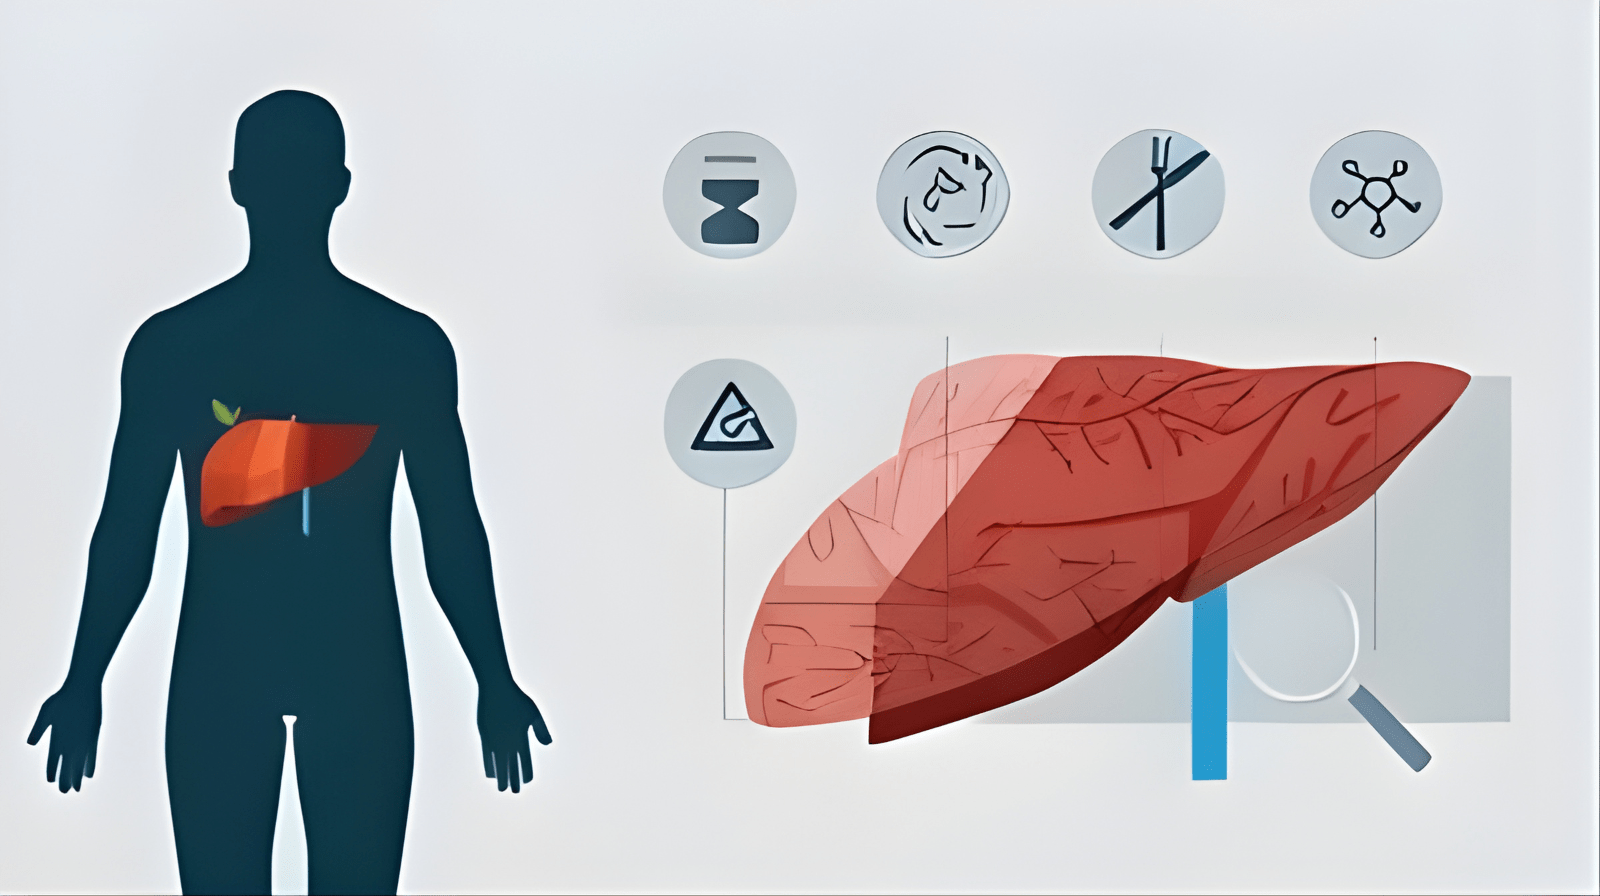

Treatments for MASLD (Metabolic dysfunction-Associated Steatotic Liver Disease)

Non-Alcoholic Fatty Liver Disease is increasingly common worldwide and linked to obesity, diabetes, and metabolic syndrome. Recent research underscores that MASLD treatment centers on lifestyle modification and drug therapies targeted at metabolic risk factors.